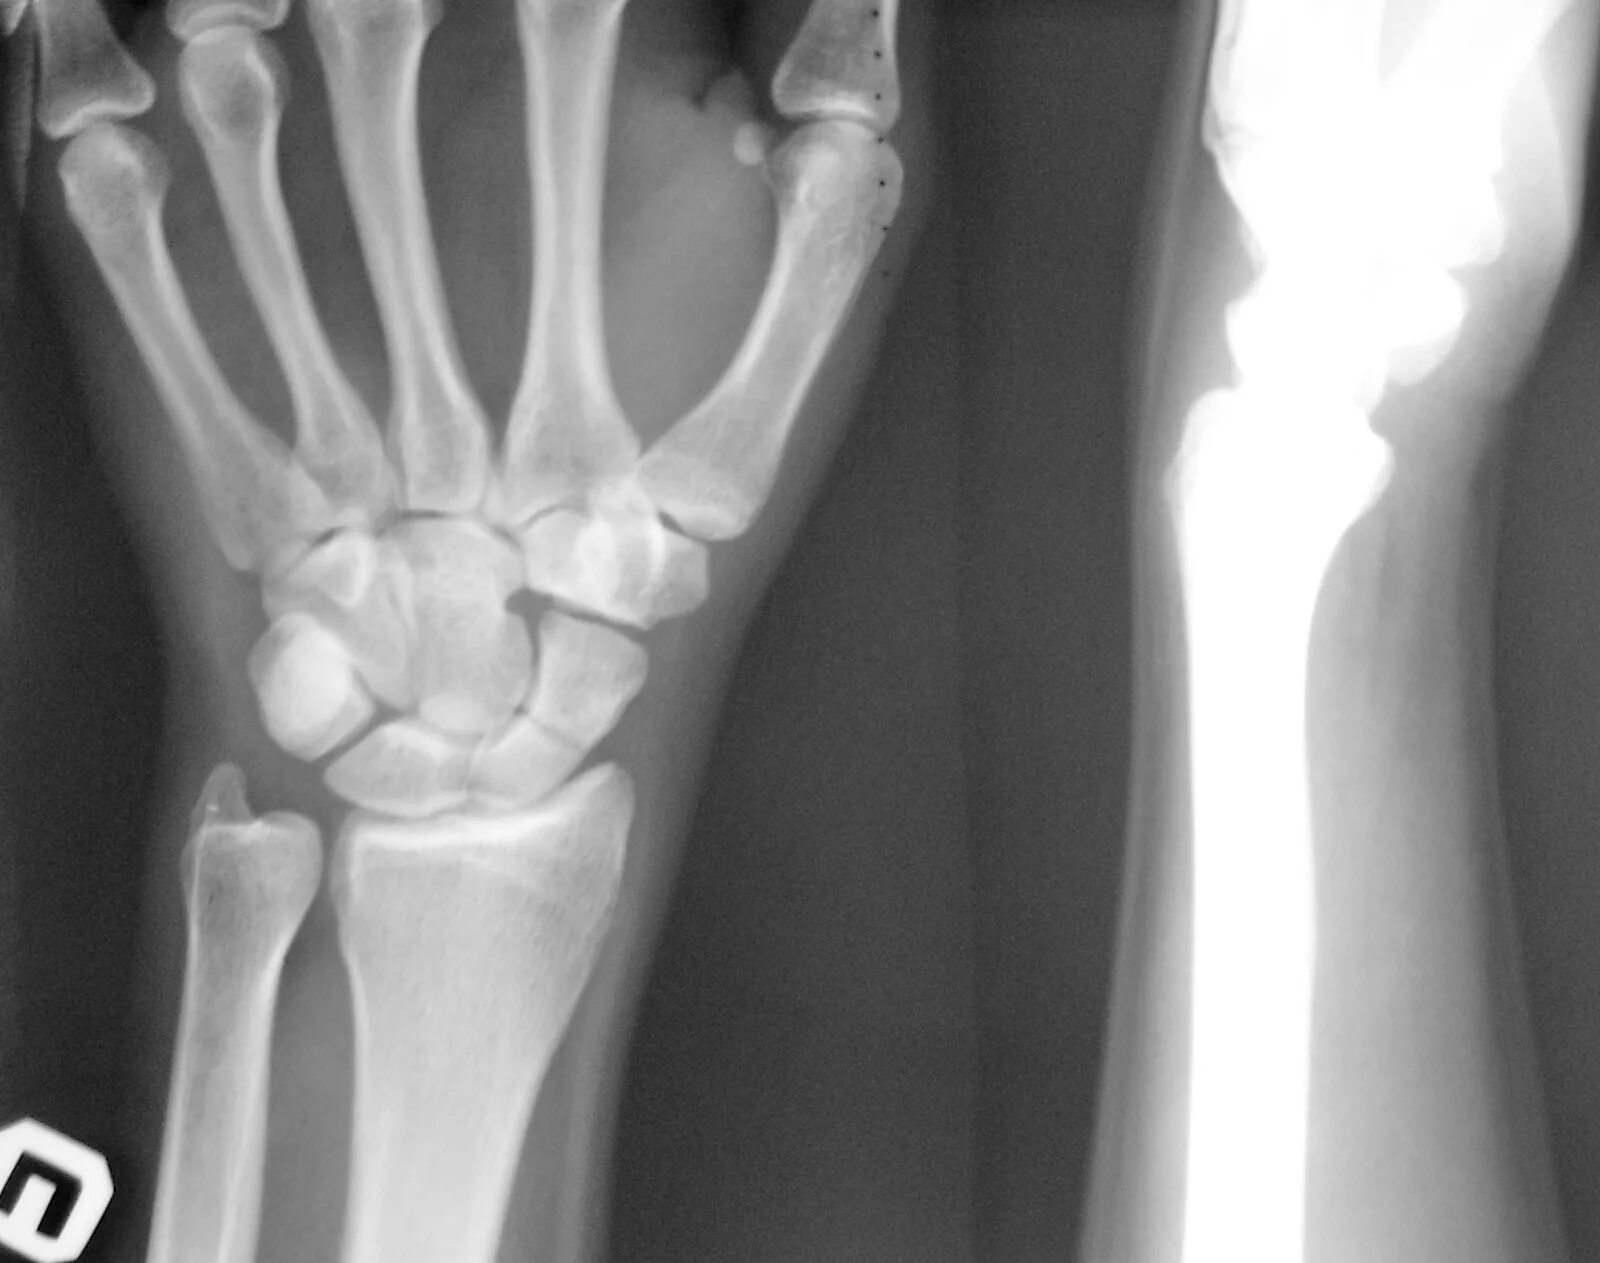

Растяжение лучезапястного сустава мкб